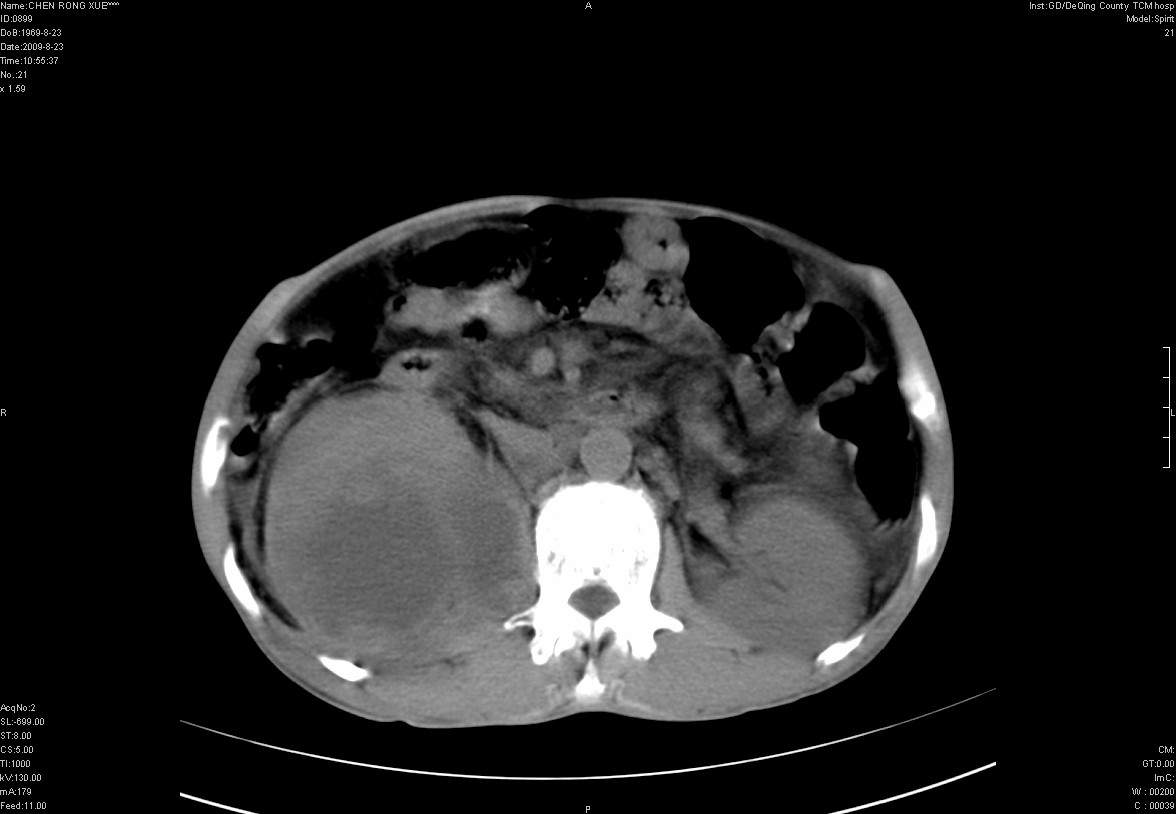

以下是引用zxl51642在2009-8-23 12:56:00的发言:[br]1、肝硬化、脾大;2、慢性胆囊炎;3、右肾占位并右侧腰大肌受侵,考虑恶性可能性大,建议增强扫描进一步检查。

以下是引用qiuleiyu在2009-8-23 15:17:00的发言:[br]1、慢性肝病,肝硬化,脾大,门脉高压。胆囊小结石。[br]2、右肾明显肿大,伴片状低密度灶,累及右侧腰大肌,肿瘤及炎症性病变皆有可能大,建议增强。

以下是引用zjzjr在2009-8-23 17:42:00的发言:[br]1、慢性肝病,肝硬化,脾大,门脉高压。胆囊小结石。[br]右肾脓肿波及肾周,建议增强

以下是引用dyqct在2009-8-23 16:53:00的发言:[br][quote]以下是引用qiuleiyu在2009-8-23 15:17:00的发言:[br]1、慢性肝病,肝硬化,脾大,门脉高压。胆囊小结石。[br]2、右肾明显肿大,伴片状低密度灶,累及右侧腰大肌,炎症性病变可能,建议增强。